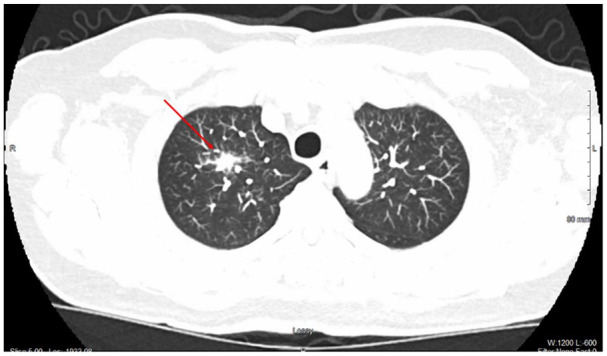

支气管相关淋巴组织(BALT)淋巴瘤是结外边缘区b细胞淋巴瘤的一种罕见亚型,占不到5%的病例。它通常是惰性的,通常是由于不相关的原因通过影像学检查偶然发现的。我们提出的情况下,一个72岁的男性胸主动脉扩张史已知,谁被发现有一个针状右上叶(RUL)肺结节的监测成像。他仍然无症状,没有体质或呼吸道症状。正电子发射断层成像显示RUL结节摄取轻度增加(标准化摄取值2.4),未见纵隔或肝门淋巴结病变。支气管镜活检,组织病理学和免疫组织化学显示低级别b细胞非霍奇金淋巴瘤,CD20和BCL2阳性。流式细胞术证实单克隆b细胞增生,荧光原位杂交分析证实BIRC3-MALT1易位,与BALT淋巴瘤一致。患者分期为IE,考虑到其疾病的局限性和无症状性,决定采取保守治疗和主动监测。虽然治疗方案可能包括手术、放疗、免疫治疗或化疗,但由于这种淋巴瘤的罕见性和异质性,对最佳方法尚无共识。在许多没有症状的早期病例中,“观察和等待”策略是合理的。该病例强调了将BALT淋巴瘤纳入偶发性肺结节鉴别诊断的重要性,并强调了提高认识和研究以建立标准化治疗方案的必要性,每个病例都为指导未来的管理策略提供了有价值的见解。

Bronchus-associated lymphoid tissue (BALT) lymphoma is a rare subtype of extra-nodal marginal zone B-cell lymphomas, accounting for less than 5% of cases. It is typically indolent and often discovered incidentally through imaging studies performed for unrelated reasons. We present the case of a 72-year-old male with a known history of thoracic aortic dilatation, who was found to have a spiculated right upper lobe (RUL) pulmonary nodule on surveillance imaging. He remained asymptomatic, with no constitutional or respiratory symptoms. Positron emission tomography imaging demonstrated mildly increased uptake (standardized uptake value 2.4) of the RUL nodule, and no mediastinal or hilar lymphadenopathy. Bronchoscopic biopsy with histopathology and immunohistochemistry revealed a low-grade B-cell non-Hodgkin's lymphoma, with CD20 and BCL2 positivity. Flow cytometry confirmed monoclonal B-cell proliferation, and fluorescence in situ hybridization analysis identified the BIRC3-MALT1 translocation, consistent with BALT lymphoma. The patient was staged as IE, and a decision was made for conservative management with active surveillance, given the localized and asymptomatic nature of his disease. While treatment options may include surgery, radiotherapy, immunotherapy, or chemotherapy, there is no consensus on the optimal approach due to the rarity and heterogeneous presentation of this lymphoma. In many early-stage cases without symptoms, a "watch and wait" strategy is reasonable. This case underscores the importance of including BALT lymphoma in the differential diagnosis of incidental pulmonary nodules and highlights the need for greater awareness and research to establish standardized treatment protocols, with each case adding valuable insight to guide future management strategies.